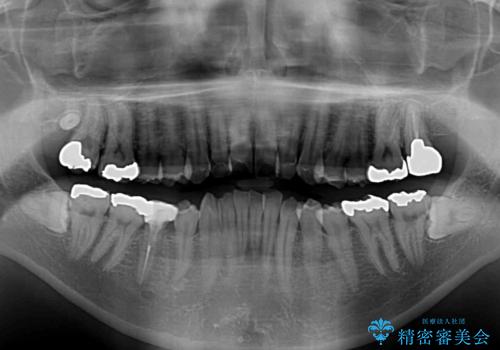

下顎に対して上顎歯列が全体的に前方に位置しており、特に右側の奥歯の咬み合わせの前後のズレが大きいため、補助装置を用いて咬み合わせを改善することとしました。

元々むし歯リスクが高かった上に、矯正治療中も磨き残しが多かったため、今後はむし歯治療を行う必要があります。